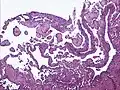

Micrograph of a kaposiform hemangioendothelioma with "glomeruloid" nodules of endothelial cells. | |

- Kaposiform hemangioendothelioma (also known as "Infantile kaposiform hemangioendothelioma"[3]) is an uncommon vascular tumor, first described by Niedt, Greco, et al. (Hemangioma with Kaposi's sarcoma-like features: report of two cases.(Niedt GW, Greco MA, Wieczorek R, Blanc WA, Knowles DM 2nd. that affects infants and young children, with rare cases having also been reported in adults. Pediatr Pathol. 1989;9(5):567-75.)[2]: 596 [3]: 1782